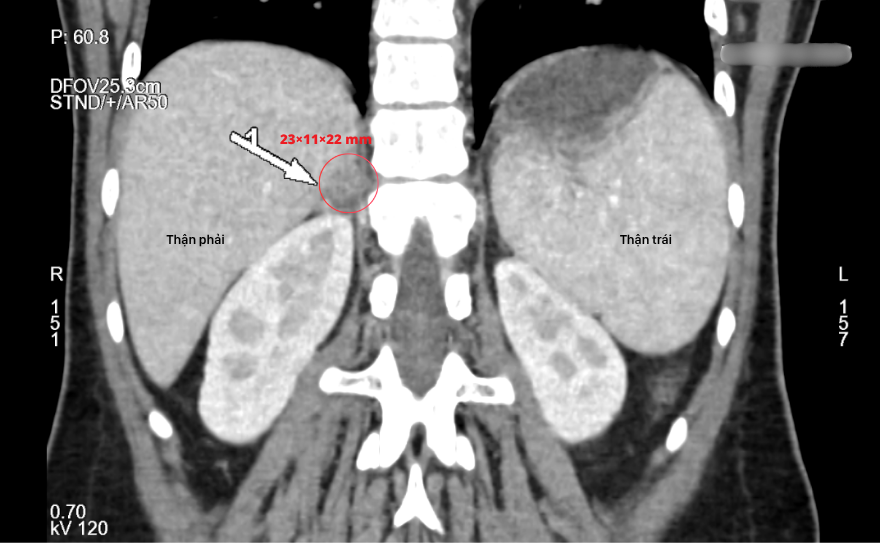

이어 시행한 복부 CT 촬영 결과, 우측 부신에서 약 23 × 11 × 22 mm 크기의 전형적인 양성 선종 소견이 관찰되었습니다. 모든 결과를 종합하여 의료진은 환자를 우측 부신 선종으로 인한 콘 증후군(Conn’s Syndrome)으로 최종 진단했습니다.

CT 영상에서 우측 부신에 약 23 × 11 × 22 mm 크기의 종양이 관찰됨.